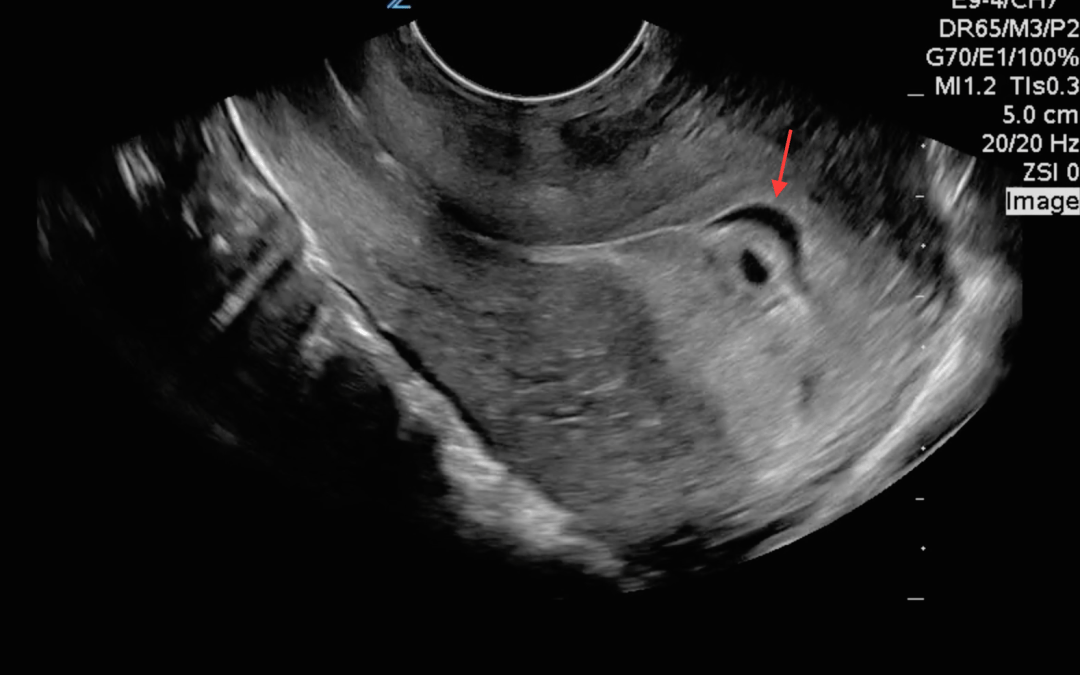

A bedside transvaginal ultrasound was performed in the ED to try and confirm an IUP. Here are the images in the longitudinal plane:

The uterus is retroverted. We know this because it is coming in from the left side of the screen and pointing down. You can see that there are two distinct fluid collections within the uterus. One is round and looks like a gestational sac. The other seems to surround the gestational sac. What do you think this fluid is?

The fluid that is seen is between the endometrium and the chorion. This is known as a subchorionic hemorrhage. Here is a picture pointing out the hemorrhage: